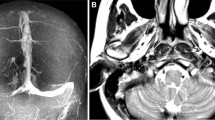

A Four-month-old boy evaluated for progressive macrocrania > 98° percentile and delayed milestones. CT scan shows external hydrocephalus, right positional plagiocephaly, and significant jugular foramen asymmetry (left > right). B At twelve months of age, MRI showed increased size of jugular foramen that remain asymmetric, confirm external hydrocephalus C with mild ventricular dilatation and right postural plagiocephaly (CVAI 10.75). D PC-MRV in coronal view confirms the different size of jugular foramen with consequent different caliber of jugular veins (left > right) and E, F 3D reconstruction of PC-MRV show a venous obstruction grading score (VOGS) of 4 due to bilateral flow gap at the level of jugular foramina

Jugular foramen stenosis

Stenosis of the jugular foramen with consequent stricture of the sigmoid sinus where it enters the jugular bulb in fact may critically interfere with the rapid ballooning of the jugular sinus (from 1 mm at birth to 5 mm at 12 months of age) that typically occurs in this age range [26], creating the anatomical condition to increase the VROut and explain the increased sagittal sinus pressure observed in EH [13]. Nevertheless, in spite of the appealing findings, the real pathophysiological mechanism of external hydrocephalus in infants is certainly more complex and should take into account the cascade of events that takes place in the intracranial cavity of an infant from birth until 2 years of age (Fig. 7A–D). In fact, brain weight quadruples in the first three years of life going from 0.36 to 0.38 kg (F/M) at birth to 1.09–1.27 kg (F/M) between 31 and 43 months [32]. Therefore, global cerebral blood flow increases following a linear correlation between age and weight in the first year of life [33, 34] even if brain perfusion remains relatively stable around 25 mL/min/kg body weight. This increase in blood flow impacts against the significantly smaller mean JF area with consequent uni-/bilateral reduced dural sinus volume, resulting in increased VROut with dilatation of cortical veins and of the sagittal sinus (arrow 5), increased capillary bed resistance, and consequent increased CSFROut due to altered CSF resorption at the level of the capillary bed (Fig. 8) [26, 26, 35]. The significantly smaller mean of jugular foramen size in patients with external hydrocephalus, if confirmed by further CT and MR studies, seems to be only a very small element but can play a very strategic role in this pathophysiological cascade of events that is quite well accepted and recognized in achondroplasia [19, 29] and syndromic craniosynostosis[18].